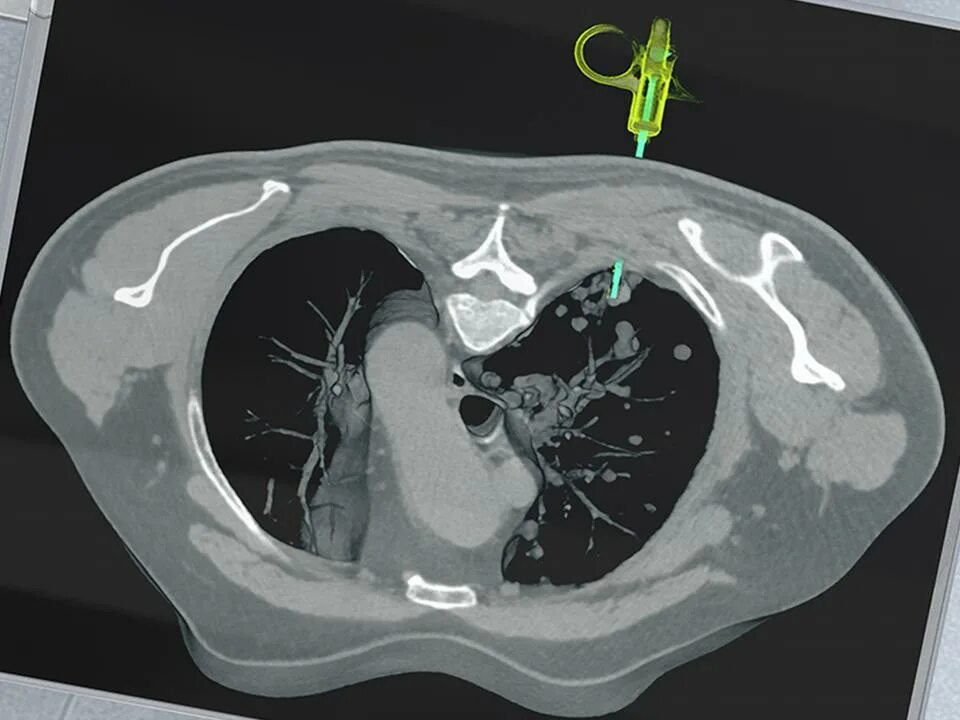

0 3 кт